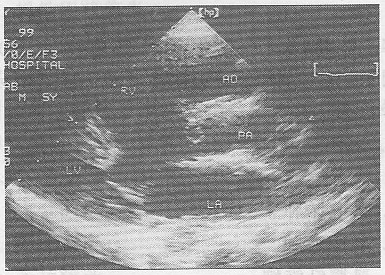

5.患者,男,30岁,常感心悸、气促,超声检查如图所示,该病例最可能的诊断是

正确答案:B 解题思路:室间隔与左室后壁非对称性肥厚。